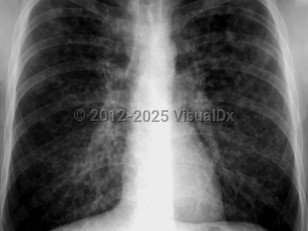

EVALI

COVID-19

Acute respiratory distress syndromeAcute respiratory distress syndrome